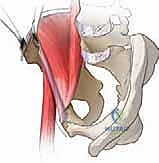

الخطوة الثانية: الشق الجراحي والوصول الآمن

يتم عمل شق جراحي تجميلي في الجزء الأمامي من الحوض. تُفصل العضلات بلطف شديد (دون قطعها قدر الإمكان) للوصول إلى عظام الحوض المحيطة بمفصل الورك، مع الحفاظ التام على الأعصاب والأوعية الدموية الرئيسية.